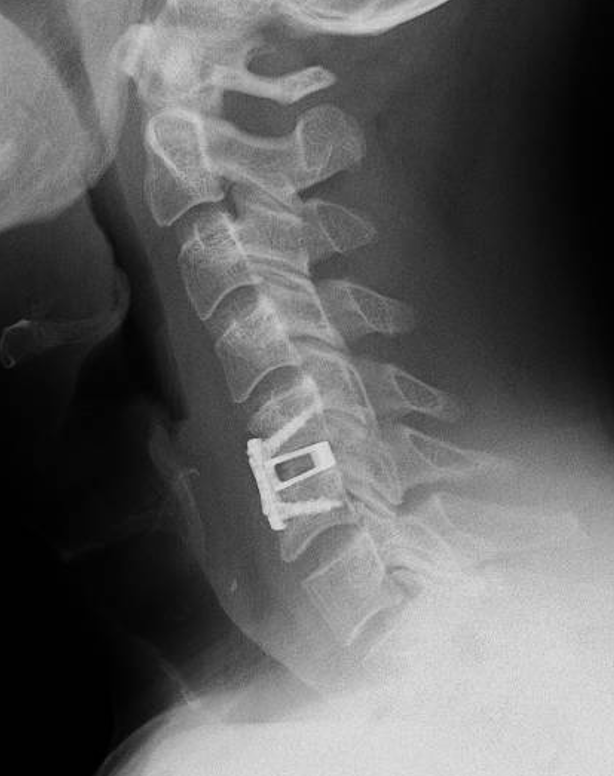

X-ray image of a human cervical spine showing a surgical implant and hardware.

What surgical options are used if needed?

When surgery is appropriate, options may include:

• Anterior Cervical Discectomy and Fusion (ACDF)

• Cervical disc replacement (select patients)

The choice depends on symptoms, anatomy, and imaging findings.